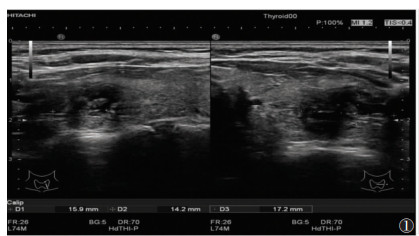

2 结果 2.1 FNAC检测结果126个结节中,102个为良性(81.0%);24个为恶性或可疑恶性(19.0%),其中,5个滤泡性甲状腺癌,7个甲状腺髓样癌和12个甲状腺乳头状癌(图 1~3)。

| 图 1 女,38岁,传统超声图像可见甲状腺体积增大,左叶可见多发性结节,形态不规则,长径约15.9 mm,峡部可见一结节,形态不规则,边缘不清晰,大小14.2 mm×17.2 mm |